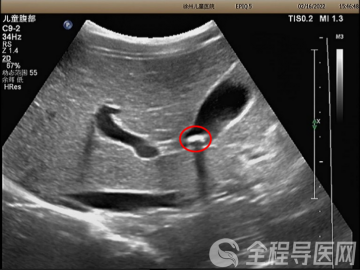

第四台 室间隔缺损、三尖瓣关闭不全、中度肺动脉高压。

患者由眼科转入。今年36岁的王女士(化名),有先天性心脏病室间隔缺损,这次因泪囊炎就诊,入院检查发现,自己的心脏病加重了,除了室间隔缺损,还出现了三尖瓣关闭不全、中度肺动脉高压,如果不及时治疗,病情会进一步加重。

薛松教授为她实施了三尖瓣成形+室间隔缺损修补术。